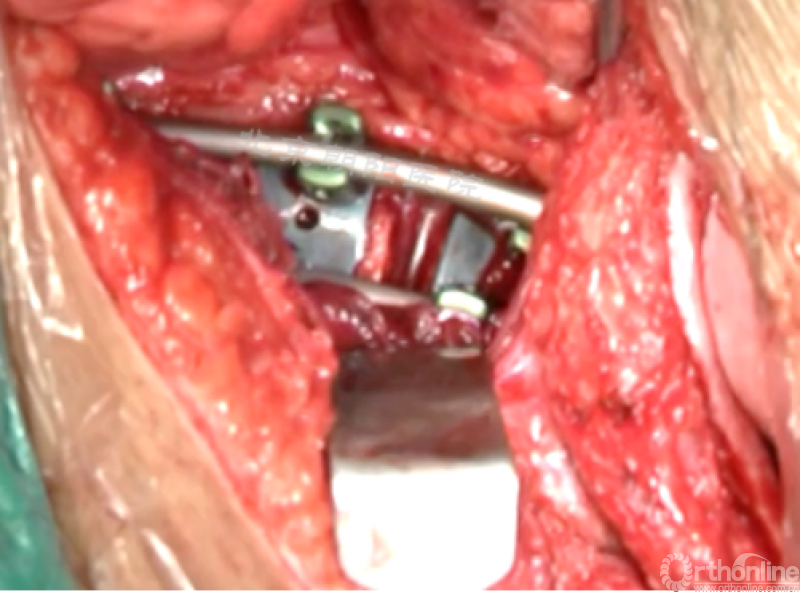

内固定选择的是5.5mm双棒系统,先置入顶椎的螺钉垫板。

置入顶椎的椎体螺钉,螺钉可置入椎体中部到后方1/3之间的范围内。

使用双棒系统时,先置入背侧的螺钉,螺钉指向椎体中线,后置入腹侧的螺钉,螺钉轻度指向后侧。形成对椎体的三角形抓持力。

胸腔侧、腹腔侧螺钉全部置入后,骨移植物植人的越靠近后纵韧带或者纤维环的后缘越好。

将预先折弯的金属棒先置入背侧。

椎间融合器经前方置入凹侧,确保腰椎前凸的恢复和冠状面畸形的矫正,将剩下的骨移植物置入椎间隙内。

置入腹侧金属棒。

使用双棒系统时先安装背侧的棒,可进行90°的去旋转,也可以直接通过前方螺钉矫正冠状面和矢状面的畸形,然后固定后方的棒,可进一步通过加压矫正冠状面畸形。

矫正后神经检测未见异常术中唤醒患者下肢活动良好,术中透视矫正效果满意、内固定位置良好。根据手术具体情况放置合适尺寸的横连接加强内固定。